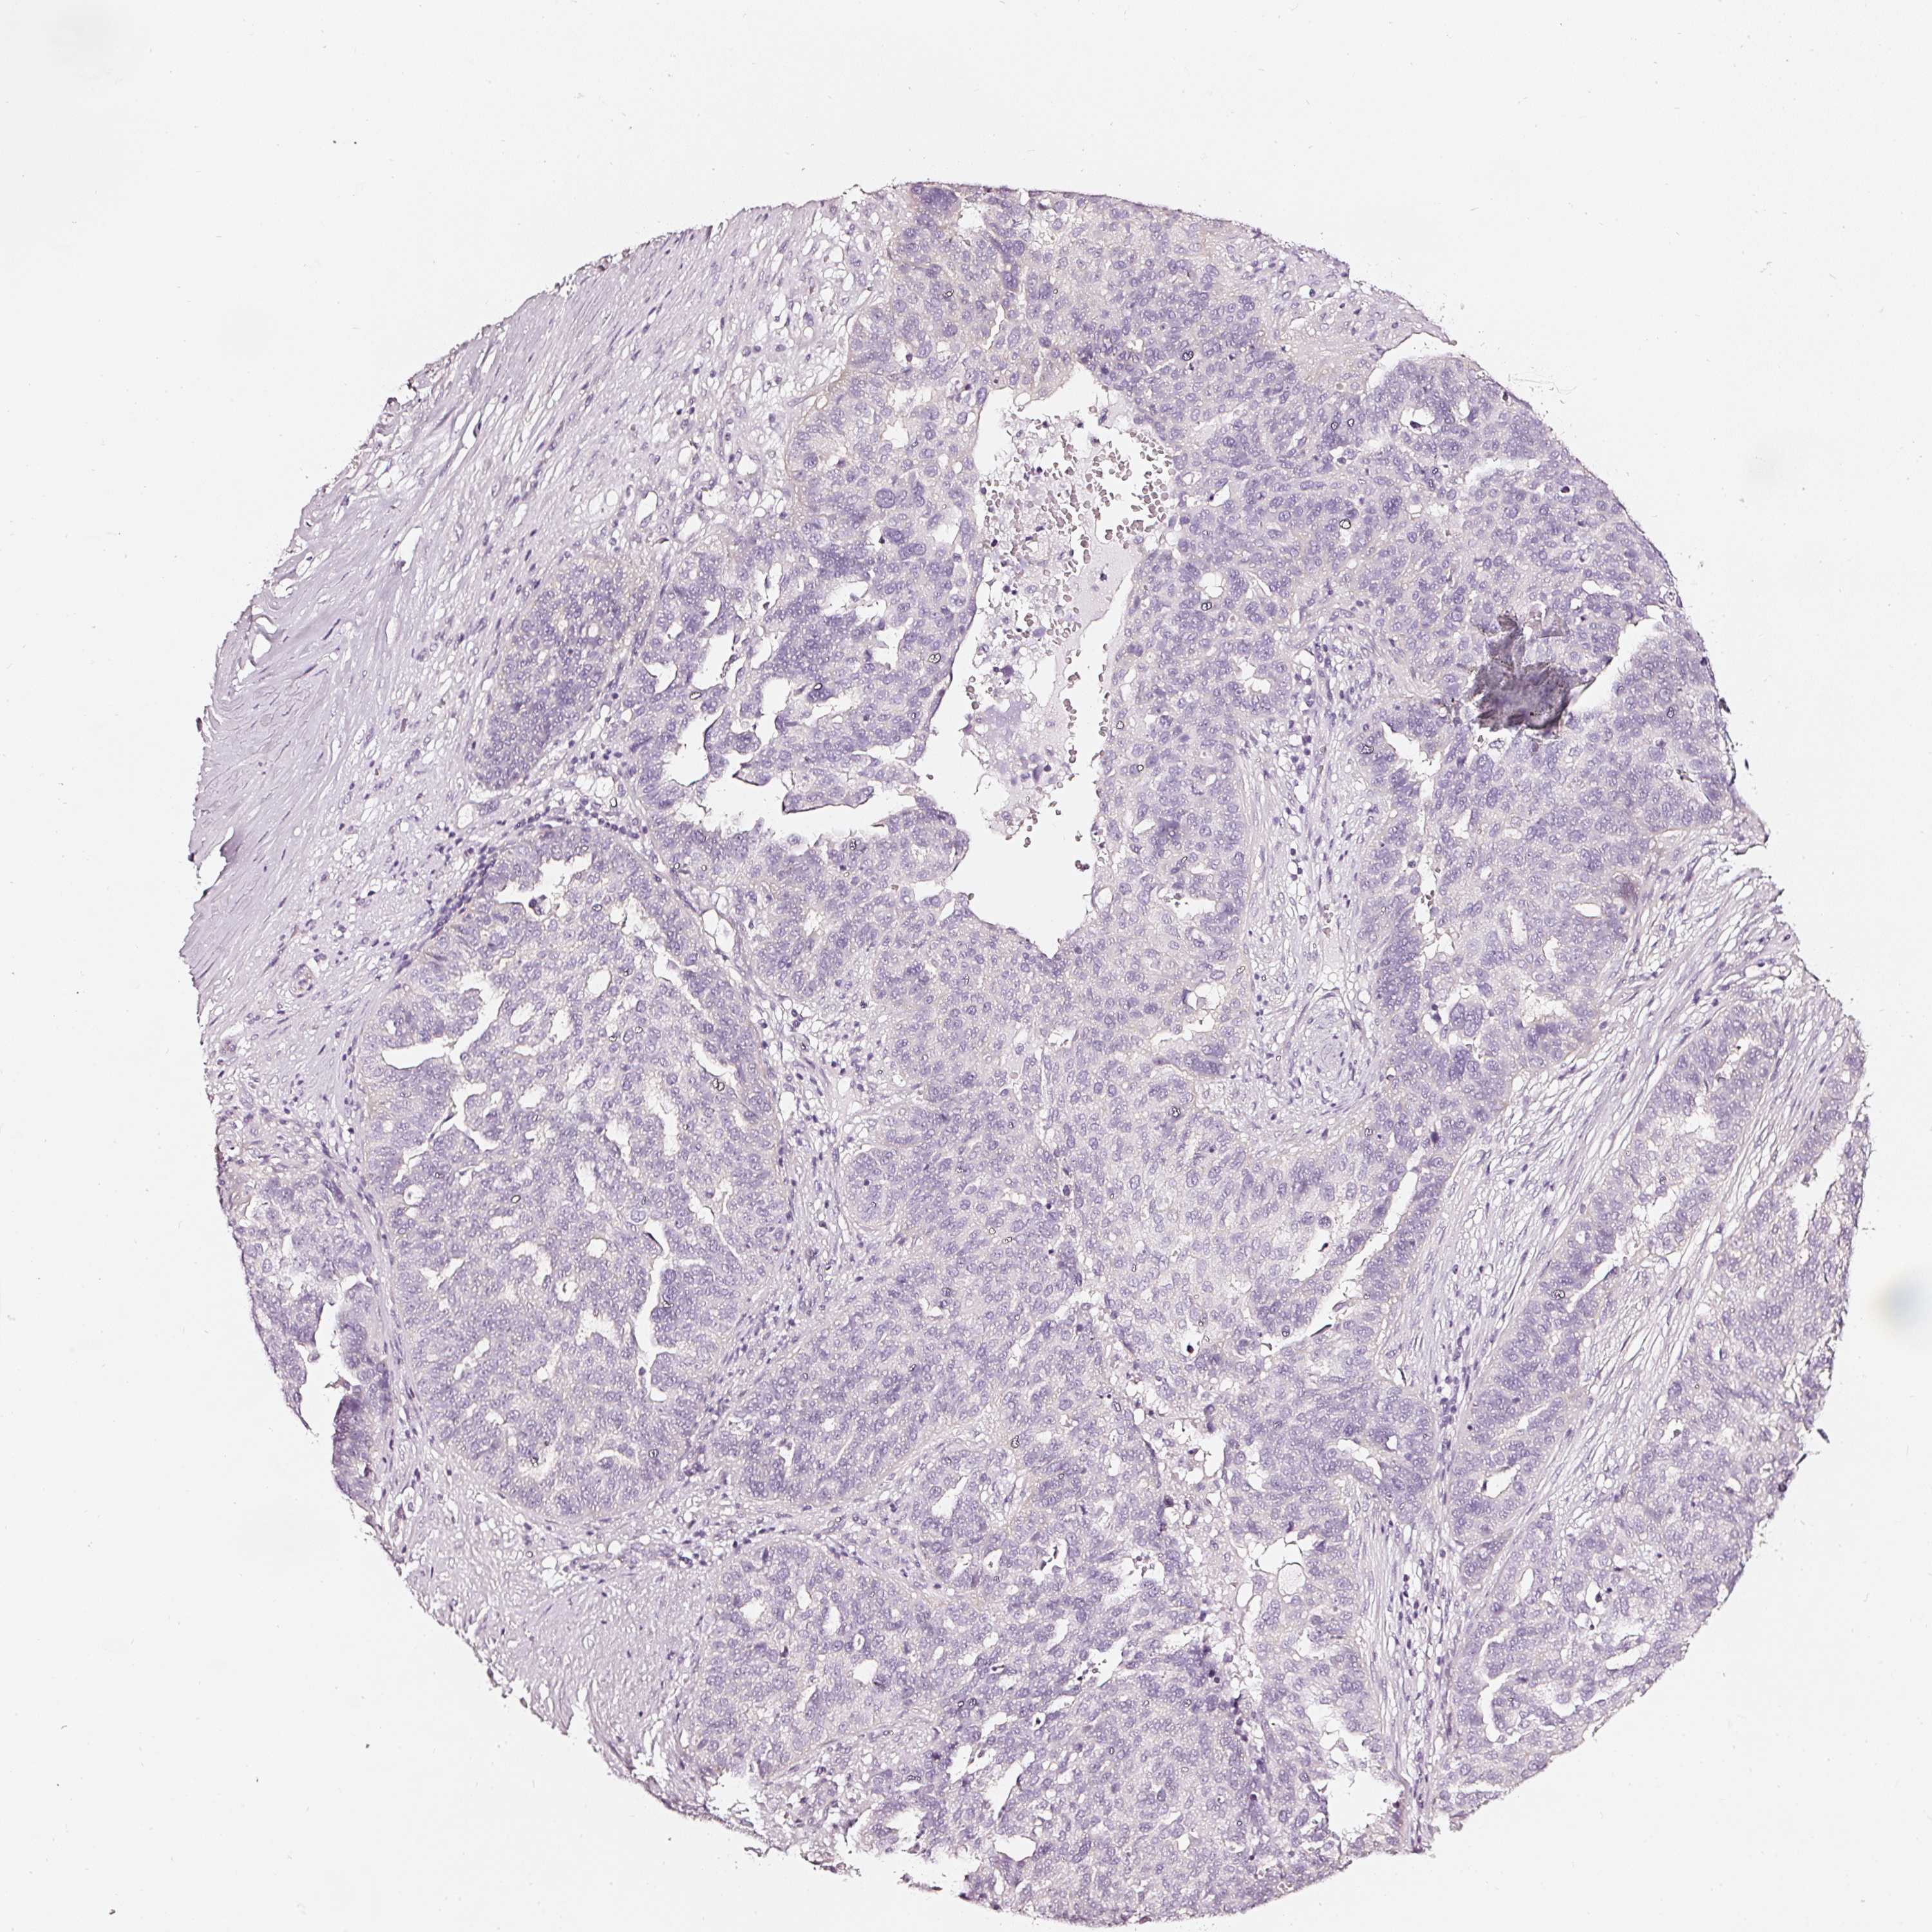

OVARIAN CANCER - Protein expressioni

A mouse-over function shows sample information and annotation data. Click on an image to view it in a full screen mode. Samples can be filtered based on level of antibody staining by selecting one or several of the following categories: high, medium, low and not detected. The assay and annotation is described here.

Note that samples used for immunohistochemistry by the Human Protein Atlas do not correspond to samples in the TCGA dataset.

Antibody stainingi

Antibody staining in the annotated cell types in the current human tissue is reported as not detected, low, medium, or high, based on conventional immunohistochemistry profiling in selected tissues. This score is based on the combination of the staining intensity and fraction of stained cells.

Each image is clickable and will lead to virtual microscopy that enables deeper exploration of all samples and also displays staining intensity scores, fraction scores and subcellular localization as well as patient and tissue information for each sample.

HPA023266

Cystadenocarcinoma, serous, NOS